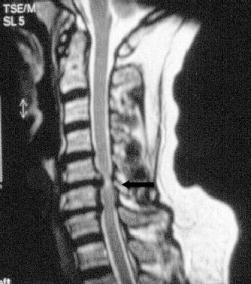

Das Gleiche gilt für Blasen-Mastdarmstörungen und Gangstörungen. Hier kann es aufgrund eines Drucks auf das Rückenmark zu bleibenden Schäden kommen. Dieses Krankheitsbild wird auch als Myelopathie beschrieben.

Durch die Untersuchung und Anamneseerhebung ergeben sich wichtige Hinweise auf die Ursachen der Beschwerden. Hieran orientiert sich auch maßgeblich die Empfehlung für oder gegen eine Operation. Ergänzend sind häufig konventionelle Röntgenaufnahmen sowie eine Kernspintomographie sinnvoll. Knochenveränderungen werden besser mit der Computertomographie erfasst. Besteht der Verdacht auf eine Rückenmarkserkrankung oder eine Störung der Nervenfunktion wird eine elektrophysiologische Untersuchung (evozierte Potentiale) organisiert. Hierbei wird, ähnlich wie bei einem Stromkabel, die Durchgängigkeit der Nervenbahnen gemessen.